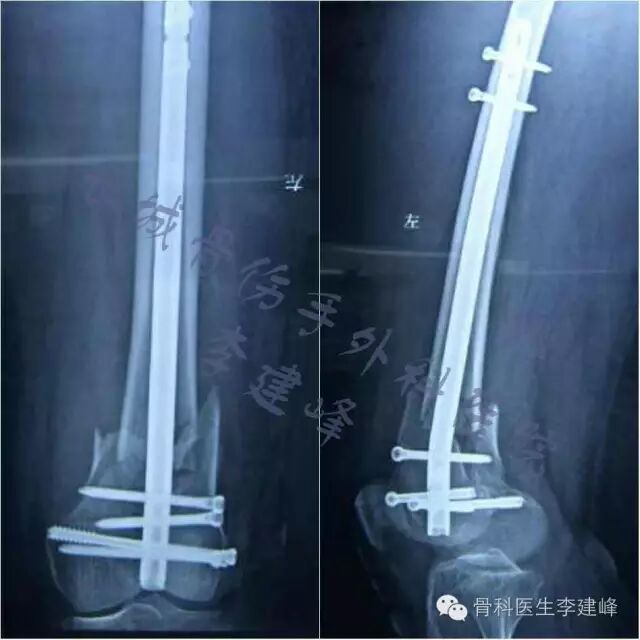

Seven case :

术前

术后